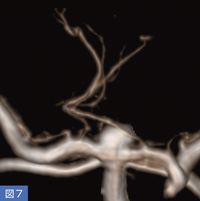

72歳、女性。未破裂脳底動脈先端部動脈瘤(図6)に対して瘤内塞栓術を行った。3D-DAで穿通枝の分岐部を確認し(図7)、塞栓術中も穿通枝の状態を確認しながら塞栓を進め、良好な塞栓を得ることができた(図8)。

図8 図6の症例の術後画像

図6の症例の術後画像